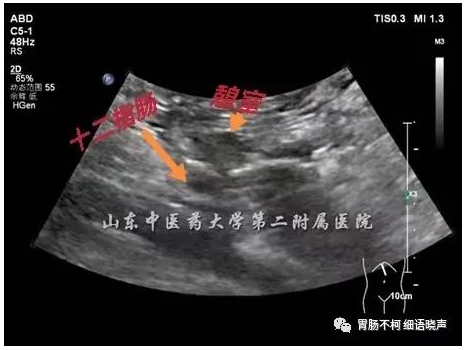

短轴切面可见十二指肠与憩室的“双腔征”: